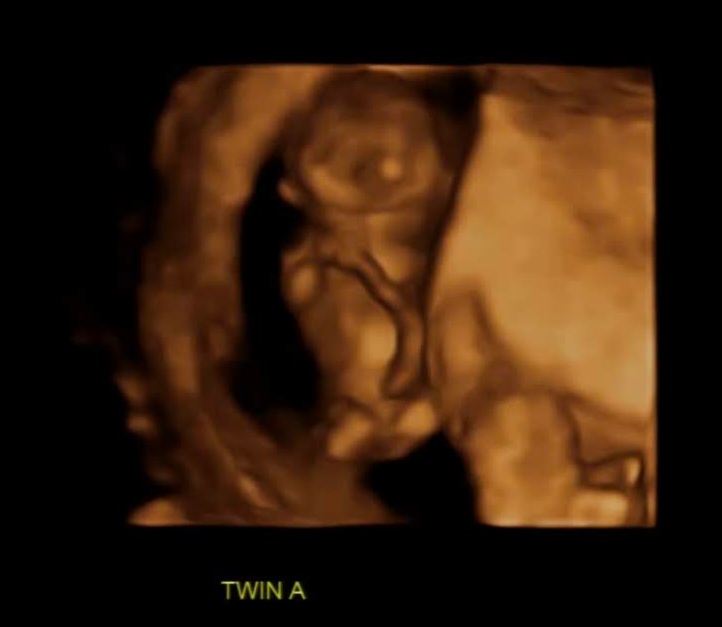

저도 쌍둥이들이 뱃속에 있을 때 두 아이의 태동 차이가 컸습니다. 한 녀석은 정말 활발히 움직였고 한 녀석은 거의 움직이지 않았는데요.

한 번은 어쩌다가 의도치 않게 앞으로 넘어지게 됐는데 순간적으로 손으로 배를 가리긴 했지만 배 부분으로 정확히 떨어졌습니다. 그러고 나서 태동이 느껴지지 않는 겁니다 너무 걱정을 했고 바로 병원을 가야 하나 고민을 했는데요. 만약에 그 상황에서 안 좋았다면 양수가 터지거나 배에 통증이 오거나 다른 이상이 생겼을 텐데 딱히 그렇지는 않았습니다. 그렇게 한 10분쯤 지났을 때 갑자기 뱃속에서 꿀렁하는 겁니다. ㅎㅎㅎ 우와 그때의 쫀쫀한 마음은 정말 잊을 수가 없습니다. 움직여 주는 고마운지요. 그런데 한 녀석은 잘 움직이지 않는 것처럼 느껴지는 거예요. 그렇게 5분이 더 지난 후에야 한 녀석이 또 움직였습니다.